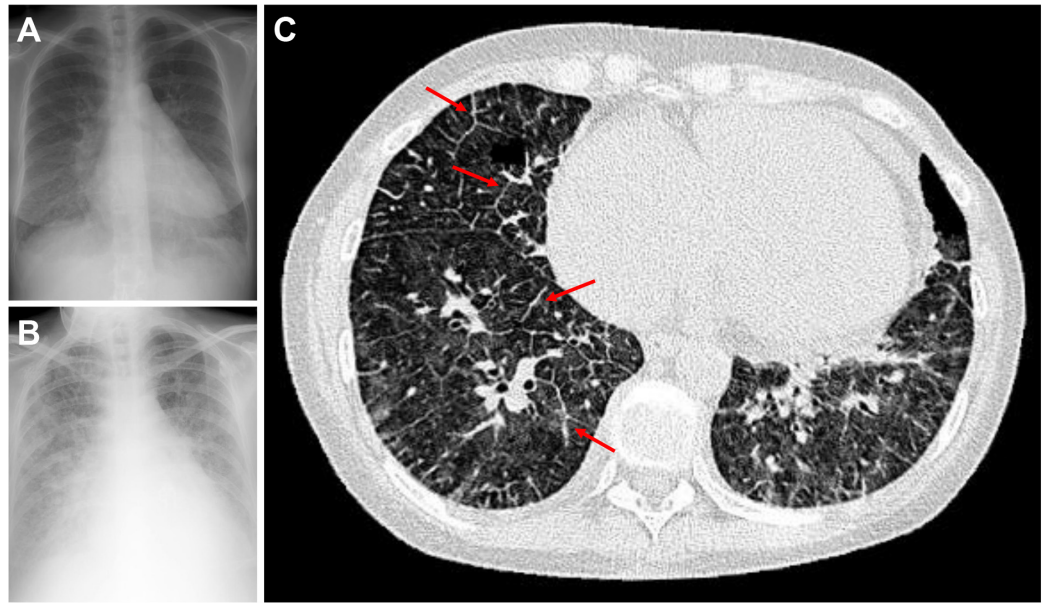

胸片示肺血管淤血,伴双侧混合性间质/肺泡浸润影(图1A)。胸部CT示双肺弥漫性磨玻璃样改变,小叶间隔增厚以下肺最为显著,纵隔淋巴结散在肿大(图1C)。

图1 影像学检查

A 启用依前列醇前胸部X线片:显示广泛双侧间质浸润影;B 启用依前列醇后胸部X线片:显示

患者因PAH出现进行性严重呼吸困难与低氧血症。初诊时的血流动力学指标提示为严重毛细血管前性PAH,但这与肺水肿影像学表现不符。左心房压力替代指标(PAWP)正常,可排除心源性肺水肿。毛细血管前性PAH患者可出现轻中度低氧血症,其原因是通气/灌注比例失调,以及心排血量降低导致的肺动脉血氧饱和度下降(最终影响动脉血氧饱和度),但此类低氧血症通常较轻。患者表现为重度PAH、与病情不匹配的严重低氧血症、PAWP正常以及肺水肿,这些特征提示可能为肺静脉闭塞病(PVOD)。影像学表现(包括小叶间隔增厚、磨玻璃样改变及淋巴结肿大)进一步支持该诊断。

依前列醇以1ng·kg⁻¹·min⁻¹ 剂量起始,随后滴定加量至6 ng·kg⁻¹·min⁻¹。数日后,患者出现低氧血症及肺水肿加重(图1B),转入重症监护室,停用依前列醇并给予利尿剂治疗。患者出现

高分辨率胸部CT显示小叶间隔增厚、磨玻璃样改变及中心小叶结节的典型三联征,进一步支持该诊断。RHC结果通常提示重度毛细血管前性PAH,但通过观察闭塞波形发现,尽管左心房压力正常,因小静脉阻力升高,仍存在肺毛细血管高压,符合PVOD的病理生理特征。左心疾病所致PAH也可累及肺静脉,并使闭塞波形衰减速度减慢,但其程度通常不及 PVOD。需注意,左心疾病相关PAH的PAWP通常升高,而PVOD患者该指标多为正常。